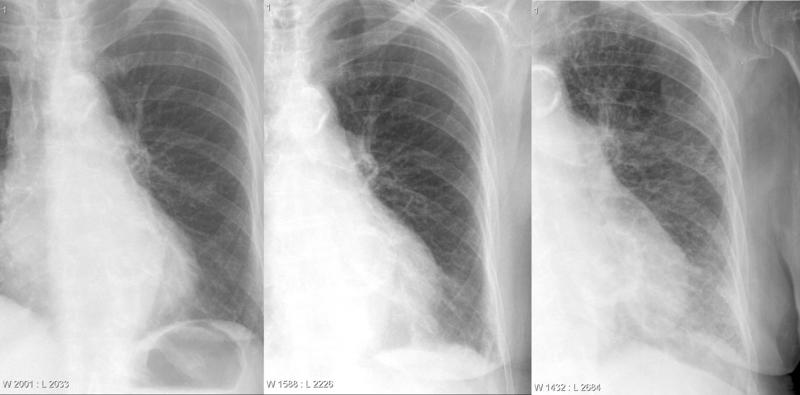

Gallery Cardiac Heart failure CHF progression

CHF progression